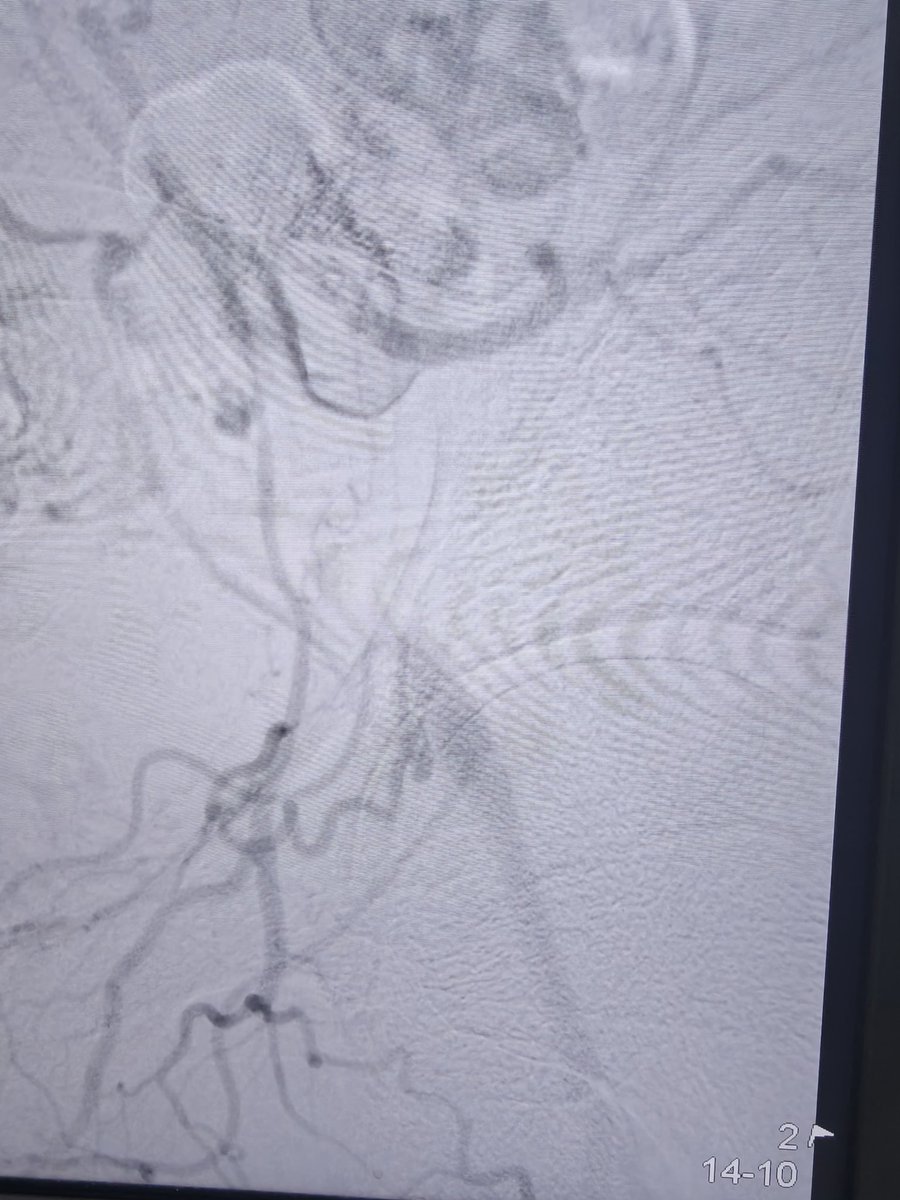

80 hrs of call #rupture #aorta #EVAR x2 #Endoanchors @MDT_Cardiac #DVT @Pen #GSW fem artery